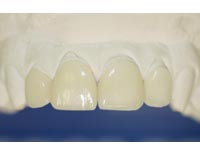

Facetas

As facetas em porcelana ultrafinas (lentes de contato) são mais uma opção para as pessoas que querem ter um sorriso mais bonito e uniforme. Com elas a estrutura dental é menos desgastada e o paciente não sente dor, já que elas são coladas dos dentes.

As chamadas lentes de contato são um tipo de faceta de porcenana, que tem o diferencial de serem muito finas (0,2mm) e exigir um mínimo desgaste dentário. As facetas comuns exigem ao menos 1mm de desgaste.

As facetas ultra- finas permitem a solução de diversos problemas estéticos nos dentes como manchas e descoloração. Além disso, elas podem fechar espaços entre os dentes, melhorar um sorriso sem o uso de aparelho ortodôntico.

As lentes de contato para os dentes possuem uma grande resistência ao desgaste e não sofrem com alterações de cores, deixando o resultado mais natural. Para manter a integridade da faceta, o paciente deve manter sua higiene bucal e tomar cuidado com alimentos muito duros.

Como alternativa às facetas ultra-finas podemos realizar facetas em resina aplicada diretamente sobre o dente (técnica direta).